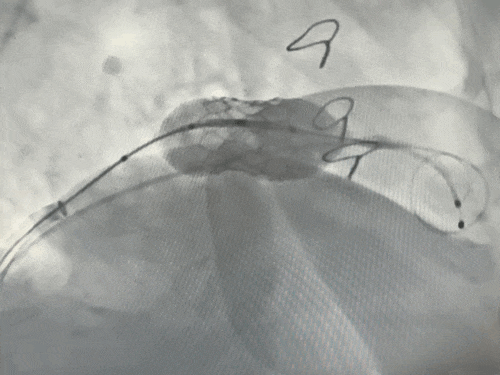

手术DSA

经左股动脉送入猪尾导管至左心室。在快速心室起搏下,使用14×40 mm球囊对衰败的二尖瓣生物瓣进行预扩张,同期行左室造影评估,判断新瓣膜植入后发生左室流出道梗阻的风险较低。

4.瓣膜植入:

将25#球囊扩张式瓣膜输送系统沿加硬导丝送至二尖瓣环位置。在TEE及DSA多角度共同确认下,精确定位。在RVP下,快速充盈球囊,将新瓣膜成功释放并固定于原生物瓣环内。即刻TEE及造影评估显示:人工瓣膜位置良好,功能正常,未见瓣周漏,左室流出道通畅。

释放瓣膜

术后复查左室造影:二尖瓣反流完全消失,瓣膜功能良好,且成功避免了左室流出道梗阻等严重并发症